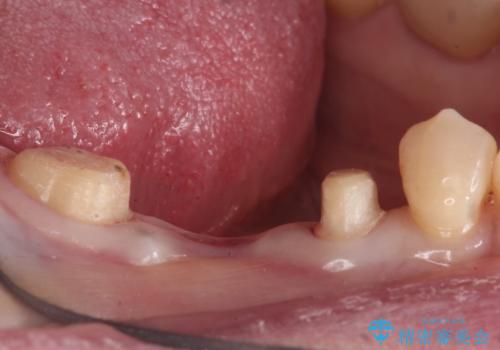

- 他院で虫歯治療に伴い初めての神経の治療を行ったところ、神経の治療自体10回以上通った上に抜歯と言われたとのことでした。

初診時には歯肉が腫れており、膿が出ている状態でした。

また、根の詰め物が根尖孔外(根の先の外の骨の部分)に盛大に漏れ出しており、歯周ポケットと根尖病巣が交通しているような状態でした。

被せ物を外したところ、歯が大変薄くなって割れており、残念ながら残すことはできないと説明しました。

初めての根の治療には見えないくらい、かなり歯が削ってあり、薄くなっていて割れても仕方ない状態でした。前の状態を見ていないので何とも言い難いですが、他の歯に比べこの歯だけ極端に状態が悪かったです。